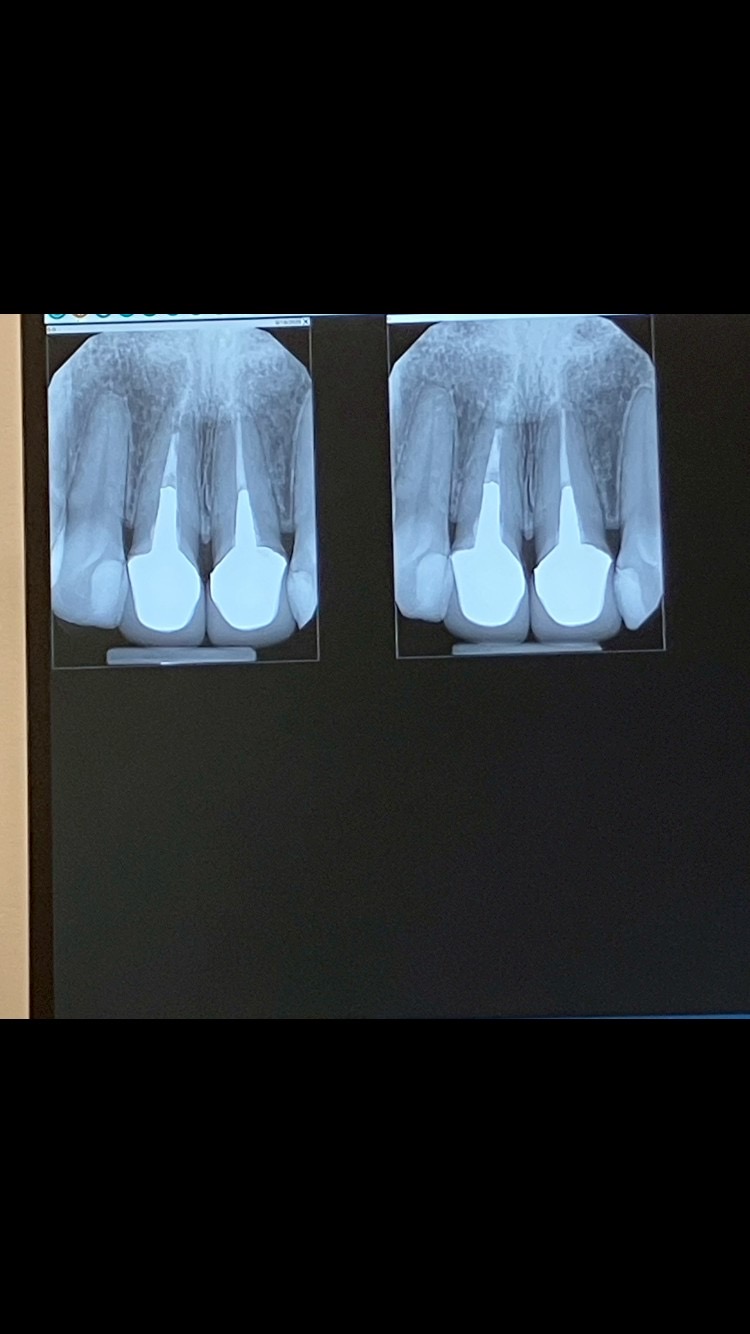

通院している歯医者さんは日本人の先生で、以前にも同様の古いメタルコアの患者さんを扱ったことがあるとの事で、 まず根管治療医を紹介されました。そこで3D/CTを撮ったところ、「入っているクラウンのメタルがかなり大きいので歯の冠部、根部の構造が損なわれている。一方の歯には充填が足りていないスぺースがあり、もう一方には少しの炎症が見られる、 上顎洞に炎症性粘膜の肥厚が認められるが副鼻腔炎は視認できない」との結果でした。

※その時の画像を添付します。

画像1IMG_6505.jpeg 画像2IMG_6504.jpeg